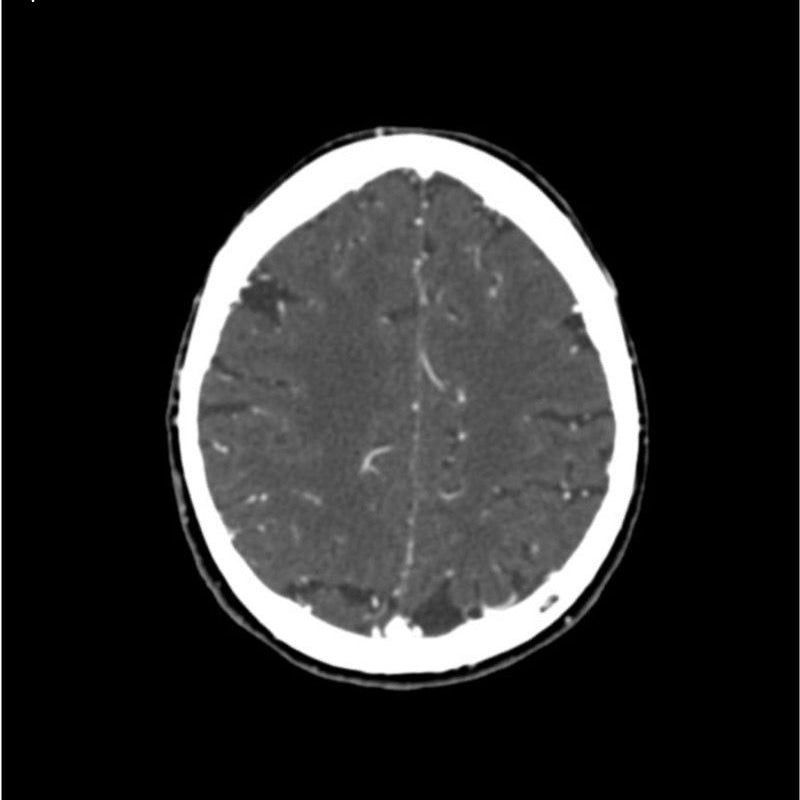

CTA Head and Neck Phantom for CT Scan and X-Ray Training

This phantom simulates a contrast medium enhanced head in arterial phase (CT angiography). The neck and upper thorax are included up to the aortic arch and the fifth thoracic vertebra. The vertex is included until approximately 0.5 cm below skin level. The thoracic phantom section excludes shoulder and back parts that are typically not part of CTA examinations. The interncal carotid artery has calcifications on both sides with moderate stenosis on the right side. Otherwise, the phantom has no significant vascular pathologies.

The phantom can be used in CT (including CBCT) to evaluate and optimize CTA imaging performance and post-processing applications such as vessel segmentation, including AI-enabled applications. It is also nicely suited for training purposes. The phantom provides a detailed and realistic simulation of vascular structures, soft and bone tissue, including small details such as lymph nodes. Air voids are filled with a cellulose-polymer composite of approx. -160 HU.

Realistic simulation of head and neck vessels up to the aortic arch, bone and soft tissues.

Calcifications of the internal carotid artery at the carotid bifurcation on both sides with mild stenosis on the right side.